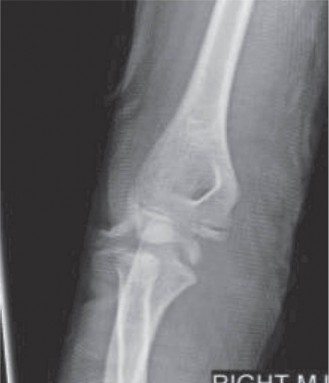

CASE 10 You are called to the emergency room to evaluate a 13-year-old male com…